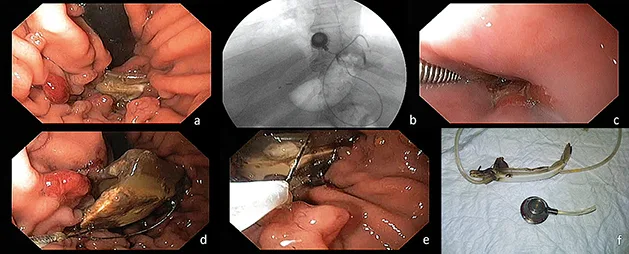

La migration intra gastrique de l’anneau gastrique ajustable est une complication survenant chez 5 à 10 % des malades au cours du suivi. Les symptômes peuvent être une reprise de poids, une infection du boîtier sous cutané, l’apparition d’une dysphagie ou de douleurs abdominales. La migration intra gastrique de l’anneau est une indication formelle à son retrait (figure 2). L’endoscopie visualise une partie plus ou moins importante de l’anneau gastrique dans la lumière gastrique en rétrovision. Pour une section/extraction endoscopique, la moitié de l’anneau doit avoir migré dans la lumière gastrique. L’intervention se déroule sous anesthésie générale, avec contrôle scopique. Un fil guide métallique est passé de part et d’autre de l’anneau visible dans l’estomac. Une gaine métallique est descendue au contact de l’anneau. L’anneau est sectionné grâce à une poignée de lithotripsie qui serre le fil métallique sur l’anneau selon le principe du fil à couper le beurre. Le boîtier de gonflage sous cutané est retiré. L’anneau peut ensuite être prudemment retiré sous contrôle endoscopique et scopique, saisi par voie endoscopique à l’aide d’une anse ou d’une pince à corps étrangers. La traction de l’anneau à travers la lumière œsophagienne doit se faire prudemment et l’aide de la scopie est parfois utile pour suivre la progression de l’anneau. Le chirurgien est souvent présent au moment de l’ablation de l’anneau car il assure le retrait du boîtier sous cutané. Le retrait chirurgical du boîtier peut également être assuré immédiatement avant le temps endoscopique. Un anneau imparfaitement migré dans la lumière gastrique sera plus difficile à retirer par voie endoscopique. La mise en place transitoire d’une prothèse œsophagienne peut aider à compléter la migration pour faciliter le geste endoscopique (3).

Figure 2 : Section et ablation endoscopique d’un anneau gastrique ajustable migré dans l’estomac

a – Visualisation en rétrovision

b – Mise en place du fil guide métallique

c – Mise en place de la gaine métallique

d – Section de l’anneau

e, f – Récupération de l’anneau